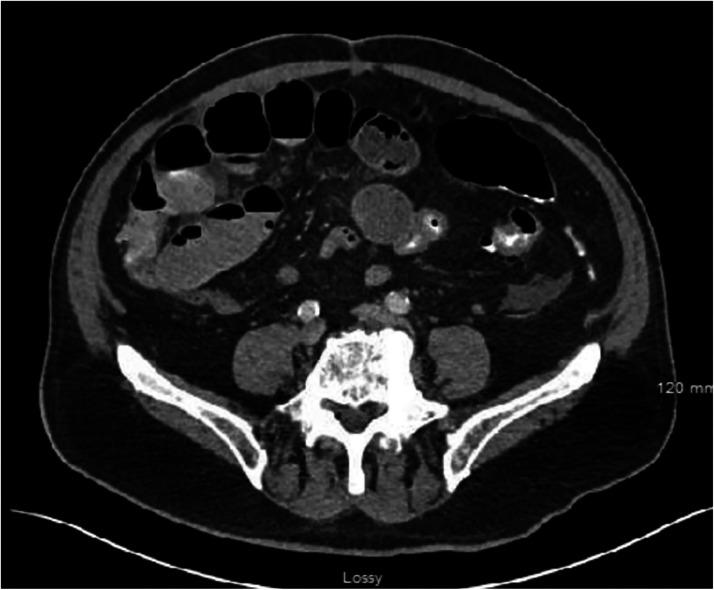

Gallstone ileus, a rare complication of cholecystitis, occurs when the distal ileum becomes obstructed by gallstone causing, mechanical bowel obstruction. Gallstone ileus with history of cholecystectomy is exceptionally rare, with few cases documented in literature. This case report details the discovery of a large, impacted gallstone 16 years postcholecystectomy. An 87-year-old male presented with progressively worsening right-sided abdominal pain over 2-3 days. Exploratory laparotomy unveiled a 2.0 cm × 2.5 cm gallstone was obstructing the terminal ileum. Patient improved remarkably postoperatively and was discharged with resolution of symptoms. A potential cause for this large gallstone impaction within the terminal ileum is gallstone ileus, which can be explained with history of intentional or unintentional subtotal cholecystectomy or long cystic duct remnant. Both rare occurrences that allow gallstone formation or passage through a chronic cholecystoduodenal fistula due to inflammatory changes. With increasing trend toward subtotal cholecystectomies and division of cystic duct closer to the gallbladder neck, this case could potentially be explained as a gallstone ileus, despite extended postoperative intervals.

摘要

胆石性肠梗阻是胆囊炎的一种罕见并发症,当远端回肠被胆结石阻塞导致机械性肠梗阻时发生。有胆囊切除术史的胆石性肠梗阻极为罕见,文献中记载的病例很少。本病例报告详细描述了胆囊切除术后16年发现的一枚巨大嵌顿胆结石。一名87岁男性在2至3天内出现右侧腹痛逐渐加重。剖腹探查发现一枚2.0厘米×2.5厘米的胆结石阻塞了回肠末端。患者术后明显好转,症状缓解后出院。回肠末端出现这种巨大胆结石嵌顿的一个潜在原因是胆石性肠梗阻,这可以用有意或无意的次全胆囊切除术史或长胆囊管残端来解释。这两种罕见情况都因炎症变化而导致胆结石形成或通过慢性胆囊十二指肠瘘管。随着次全胆囊切除术以及在更靠近胆囊颈部处切断胆囊管的趋势增加,尽管术后间隔时间较长,本病例仍可能被解释为胆石性肠梗阻。